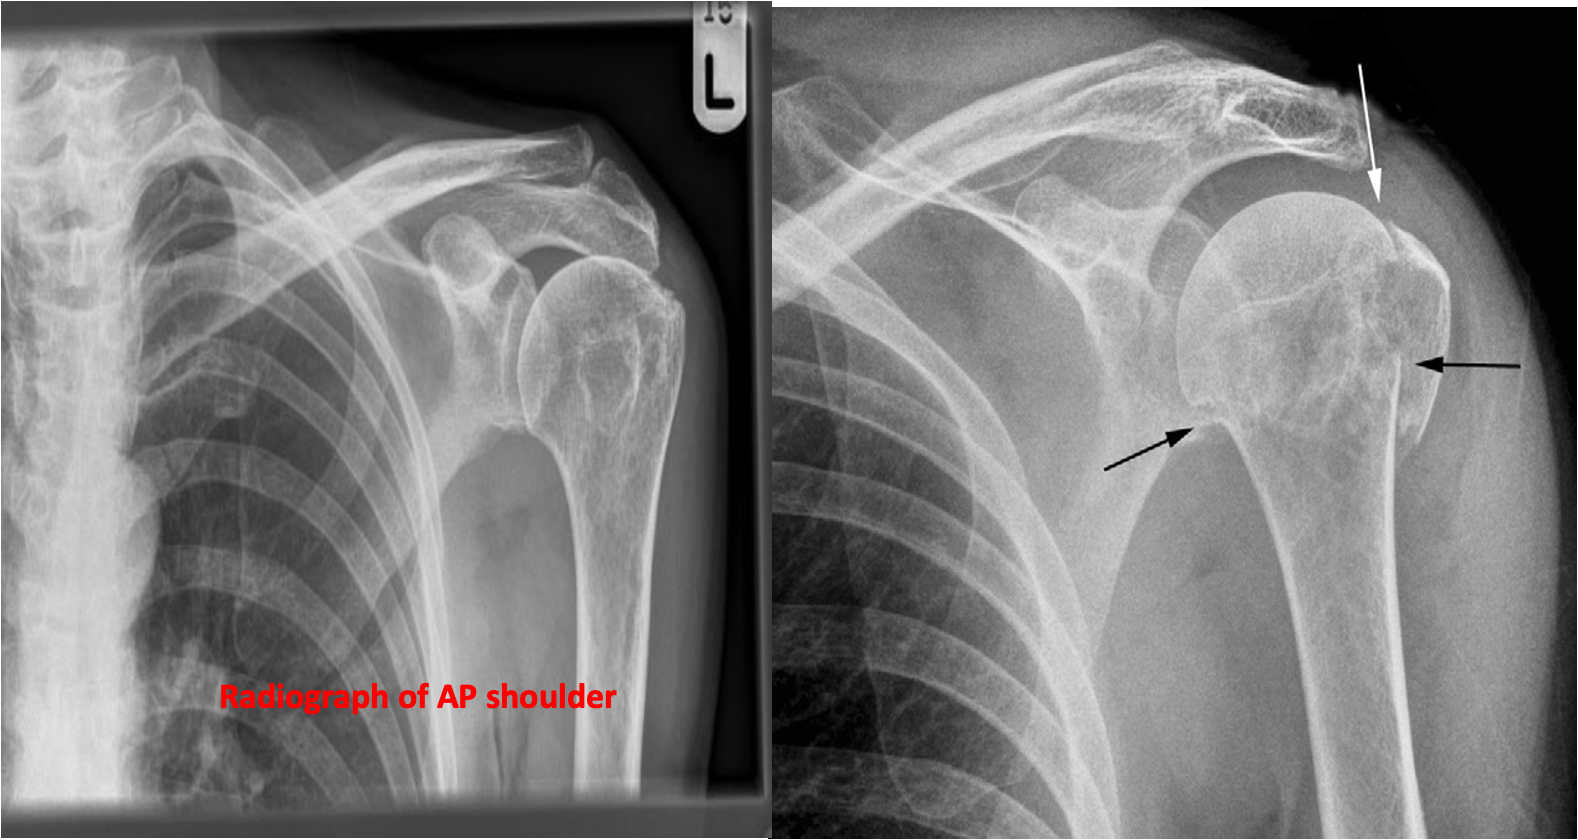

Fracture of the neck of the humerus (black arrows) is a common fracture in the elderly and may be overlooked clinically if it is impacted. The greater tuberosity is also fractured (white arrow) in this example.